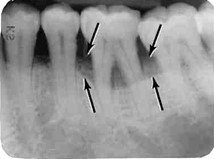

Caria dentară este reprezentată pe radiografie de o zonă gri spre negru prezentă pe suprafața dintelui. De asemenea, cariile pot ataca și dinți cu lucrări protetice chiar la joncțiunea dintre substanța naturală ș proteză.

Resorbțiile osoase sunt reprezentate de coborârea sau urcarea liniei de os sub linia normală (limita dintre coroana dentară naturală și rădăcină), lăsând zone de rădăcină descoperite și înconjurate de suprafețe negre.